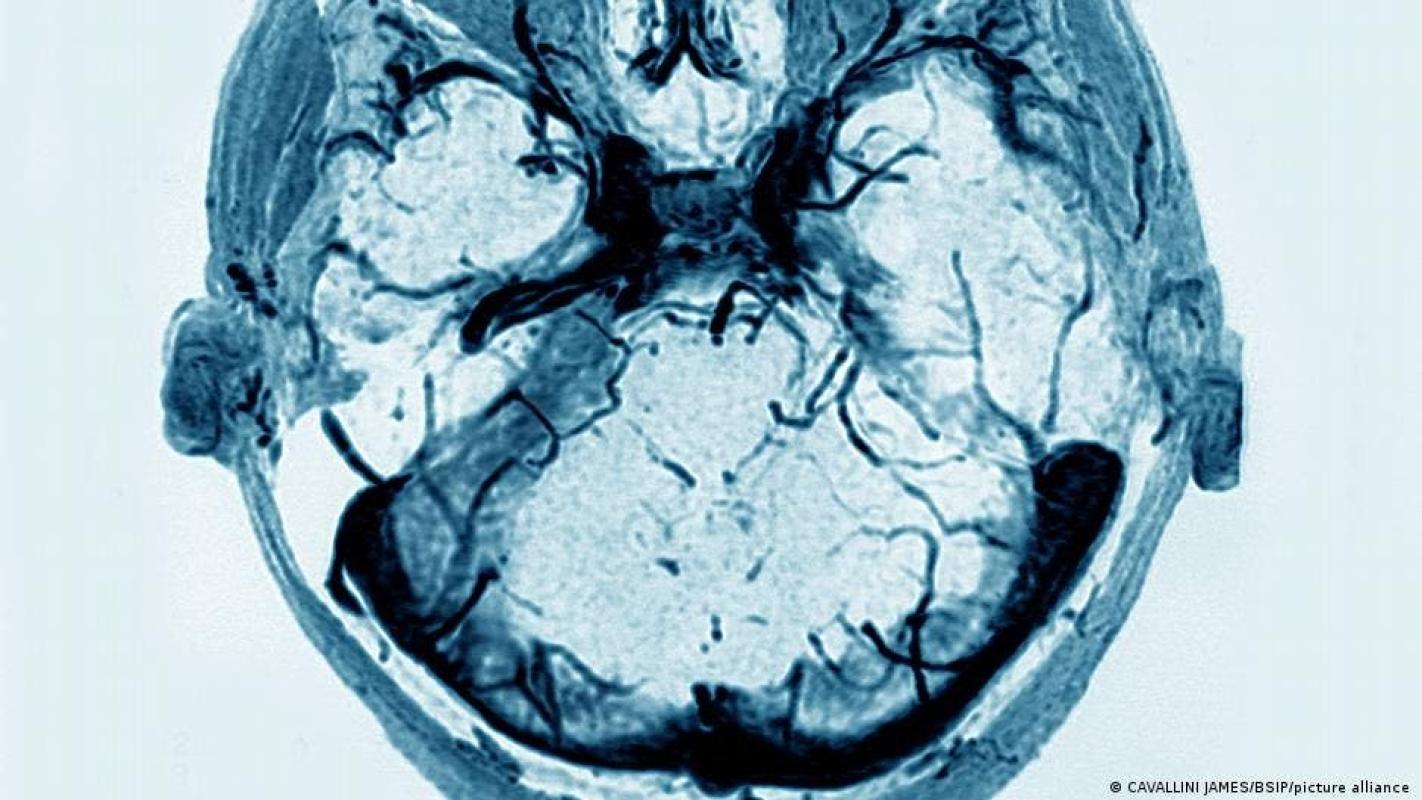

En la trombosis de senos venosos, un coágulo tapa las venas del cerebro, a través de las cuales, normalmente, la sangre pobre en oxígeno puede circular hacia el corazón. Pero, si la sangre no fluye como debiera, la presión cerebral aumenta, y se pueden producir hemorragias en el cerebro. En el peor de los casos, una trombosis de senos venosos provoca una embolia cerebral (o accidente cerebrovascular), que puede ser mortal.